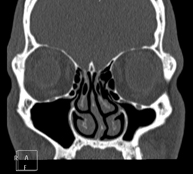

Prueba radiológica que consiste en obtener imágenes de los senos paranasales de alta definición anatómica, mediante el empleo de un equipo de TC (Tomografía Computarizada). Indicaciones: cefalea, tos crónica, mucosidad, infecciones faciales. - TC Peñascos